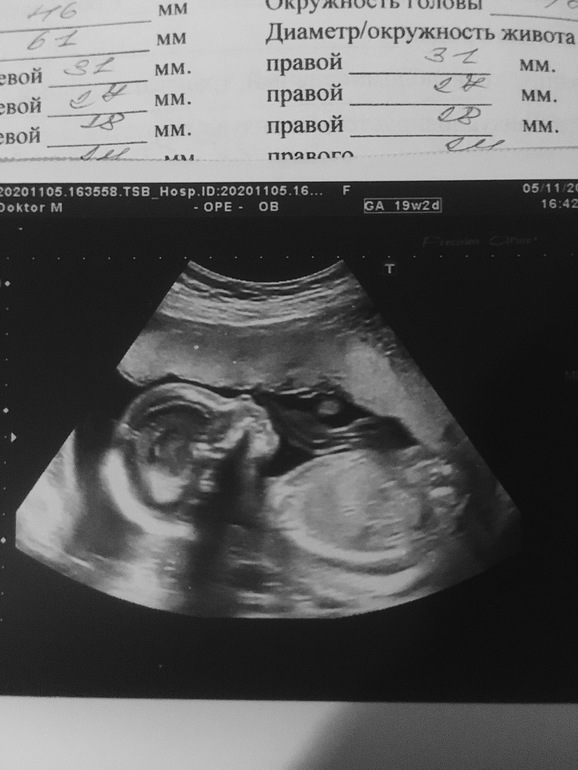

Что ж.. вот прошли и мы второй скрининг)

Парень развивается хорошо, с опережением.

Спал, лентяй и палец сосал)

340г, 21 см.

Единственное, тазовое предлежание, но говорят, к 36 неделе ещё все может изменится, да?